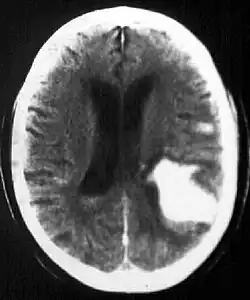

Multiple intraparenchymal hemorrhage

Intraparenchymal hemorrhage

CT-scan of intraparenchymal hemorrhage

Computed tomography (CT scan): A CT scan may be normal if it is done soon after the onset of symptoms. A CT scan is the best test to look for bleeding in or around your brain. In some hospitals, a perfusion CT scan may be done to see where the blood is flowing and not flowing in your brain.